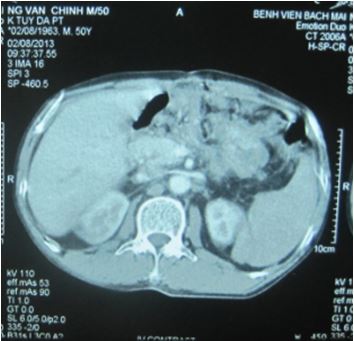

- Chất chỉ điểm u: CA 19-9: 1000UI/ml. Chụp PET/CT với 18-FGD thấy: u thân tụy kích thước 4x5 cm, tăng hấp thu FDG max SUV: 8,0 và khối thành bụng kích thước 2x3 cm tăng hấp thu FDG (hướng tới tổn thương thứ phát).

Hình 1: U thân tụy (mũi tên) trên hình ảnh PET/CT